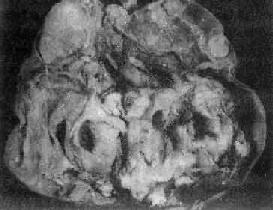

肉眼观,肿多为囊性、中等大小,表面光滑,囊内含毛发团及皮脂样物(图13-22)。囊壁较厚,内侧常有一处突起的结节或我称头节,表面被覆鳞状上皮,结节内常有毛发、牙或骨质等。肿多数为单房。镜下,可见到三胚层各种类型的成熟组织,其中以皮肤、皮脂腺、汗腺、毛囊及脂肪最多见;其次为软骨、神经胶质、神经细胞、骨及呼吸上皮;其他如甲状腺、胃肠上皮及牙等较少见。

卵巢囊性畸胎<a href=瘤"/>

图13-22 卵巢囊性畸胎

囊内充满含有毛发的黄色油脂样物